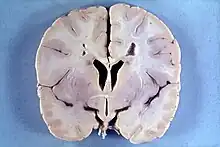

Macrocephaly (right) vs. normocephaly (left)